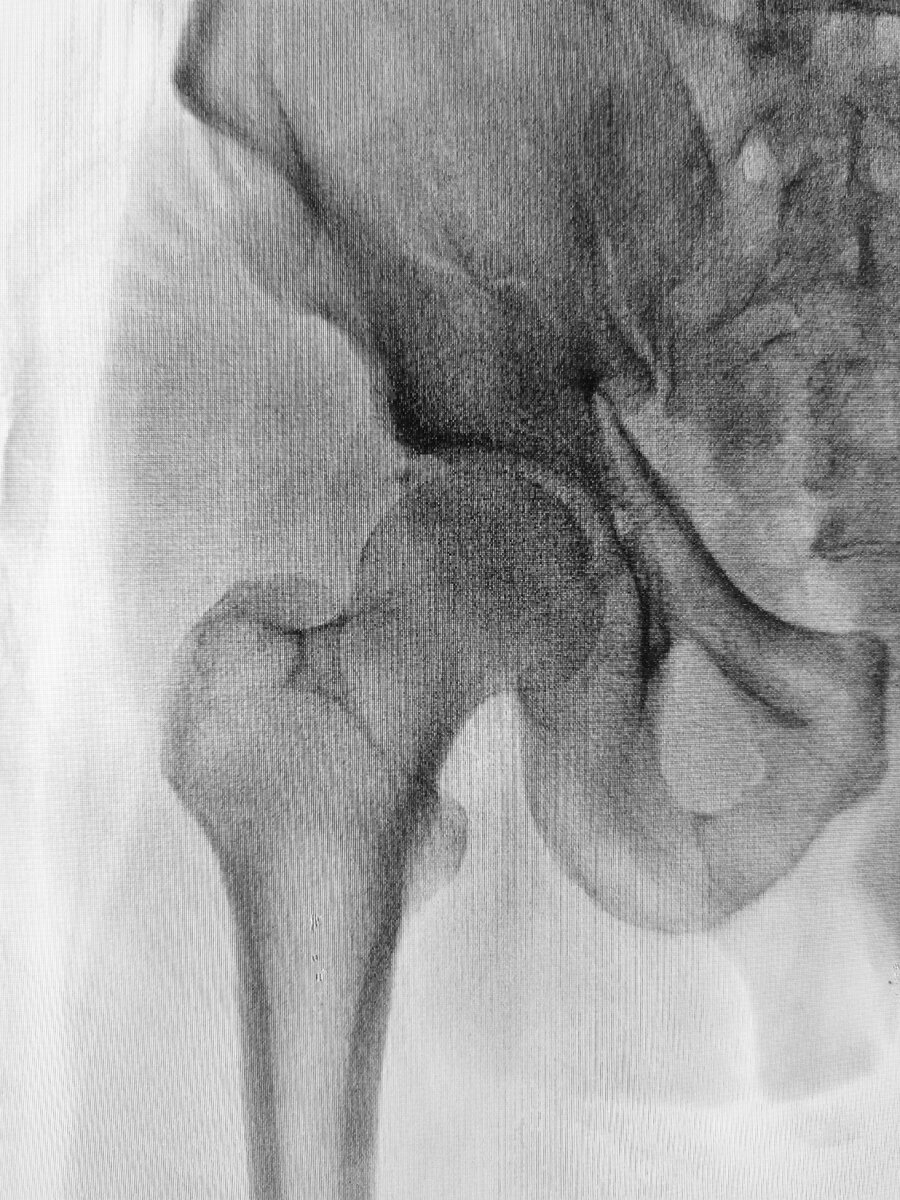

• Рентген для проверки на переломы костей.